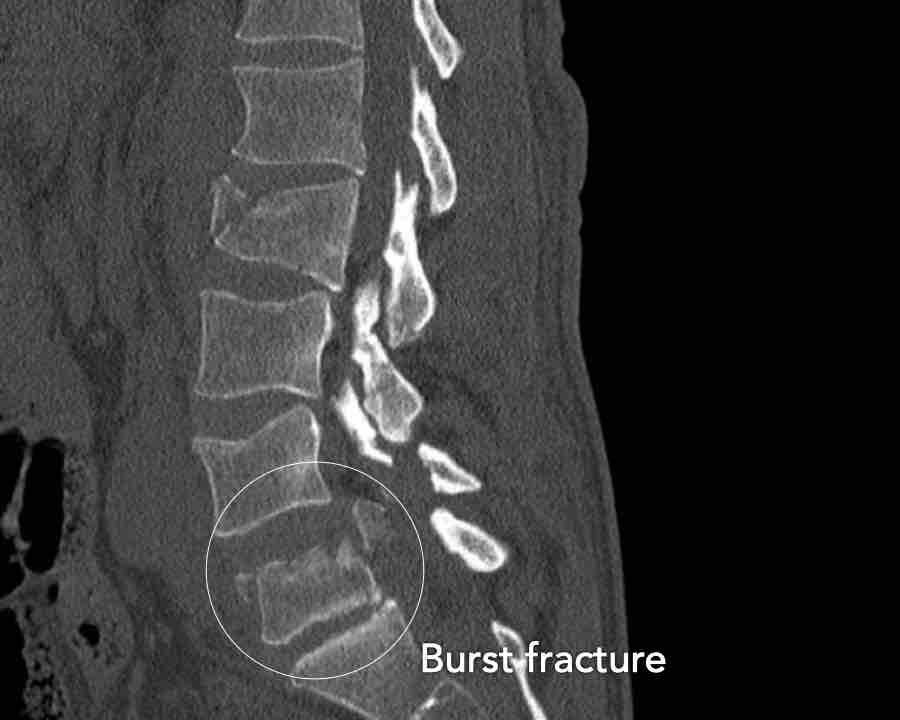

A4 Complete Burst fracture

Fracture with involvement of the posterior wall and both endplates.

A vertical fracture of the lamina can be present and does not constitute a tension band failure.

What is the highest AO-type of injury?

Findings:

- No C or B injury

- Fractures of the vertebral body with involvement of both endplates (1+1 points) and posterior wall (2 points)

Conclusion

Injury type A4

Here more examples of typical burst injuries.

Due to the axial force, the vertebral body is ‘split in half’, therefore a sagittal course of the fracture is common.

Therefore a fracture through the posterior osseous structures is possible in some type A injuries and should not always be regarded as a posterior distraction injury.

This can be confusing sometimes.